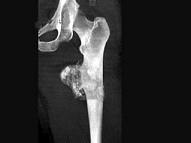

男,36岁,髋关节疼痛、肿胀,活动受限1月,结合图像,最可能的诊断是?(?)A.骨肉瘤B.软骨瘤C.股骨结核D.软骨肉瘤E.转移瘤

问题 男,36岁,髋关节疼痛、肿胀,活动受限1月,结合图像,最可能的诊断是?(?)

选项 A.骨肉瘤 B.软骨瘤 C.股骨结核 D.软骨肉瘤 E.转移瘤

答案 D